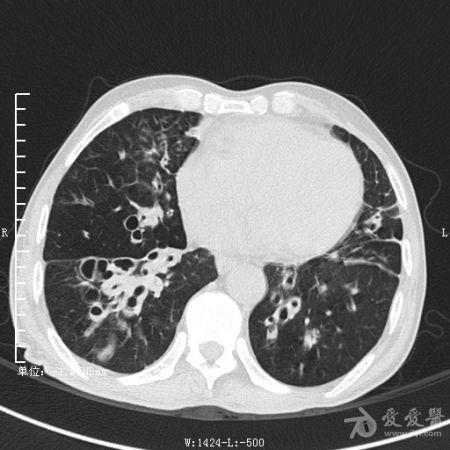

典型支气管扩张及肺水肿CT片

典型支气管扩张肺水肿